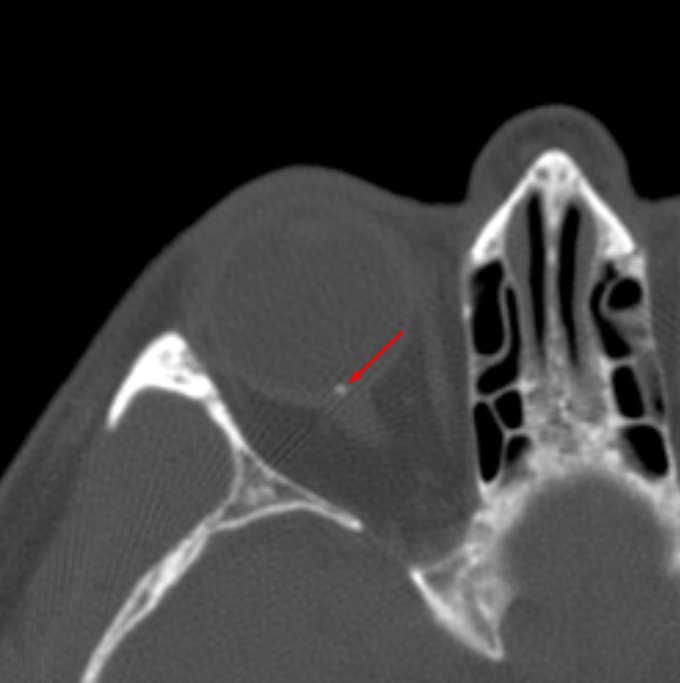

Age: 70

Sex: Female

Indication: Vision Changes